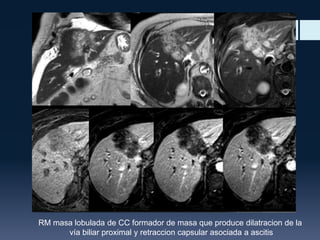

RM masa lobulada de CC formador de masa que produce dilatracion de la

vía biliar proximal y retraccion capsular asociada a ascitis

RM masa lobuladade CC formador de masa que produce dilatracion de la vía biliar proximal y retraccion capsular asociada a ascitis